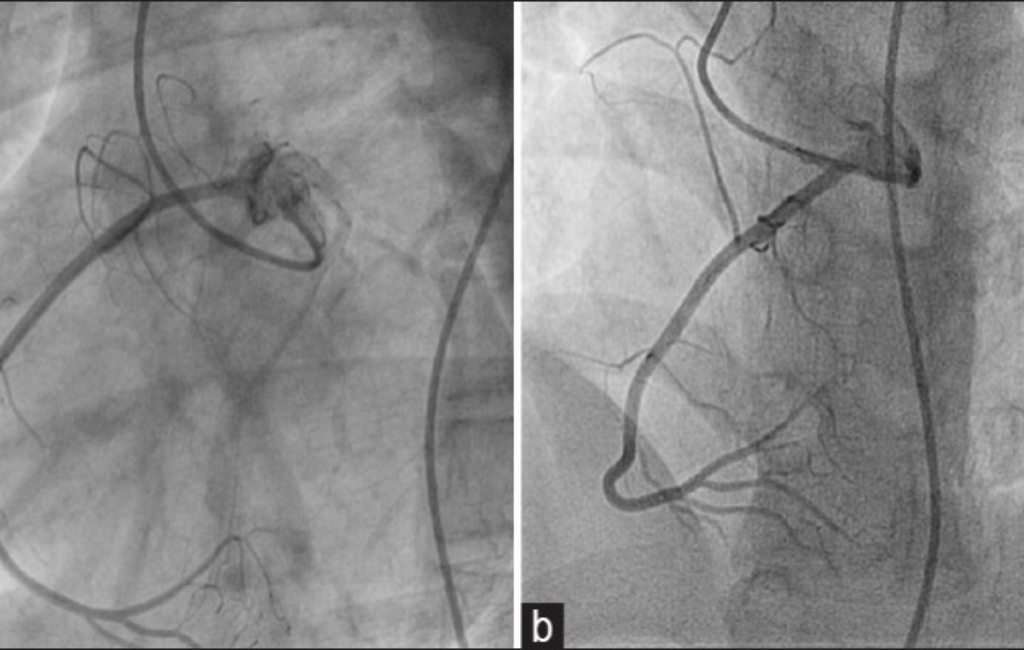

Angioplasty & Stent Placement – Restoring Blood Flow to the Heart

• Balloon Angioplasty & Stenting – Non-surgical, quick recovery treatment for heart blockages.

• Drug-Eluting & Bioabsorbable Stents – Advanced solutions for artery widening.